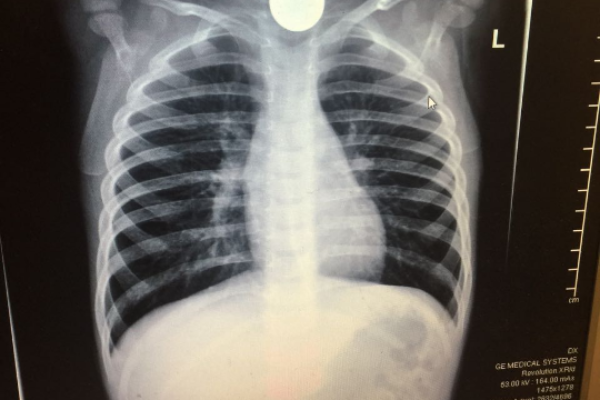

סדרת בדיקות ובכללן בדיקת רנטגן הבהירו ללא כל צל של ספק כי חפץ עגול ושטוח היה נעוץ בוושט של הפעוט. ד"ר מרדכי סליי, רופא גסטרו ילדים בכיר הוזעק בדחיפות למיון ילדים והחל בפעולות חילוץ מידיות של החפץ אשר עלול היה לגרום לסיבוכים ניכרים עד כדי התערבות ניתוחית ואף לסיכון חייו של הילד.